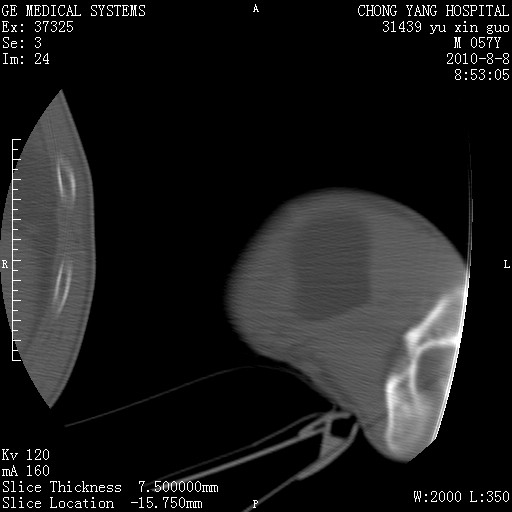

标题: CT28267:M57Y 上臂包块8年余。 [打印本页]

标题: CT28267:M57Y 上臂包块8年余。

典型脂肪瘤改变

上臂软组织内脂肪瘤。

包膜光滑、完整的脂肪密度肿块,支持脂肪瘤。